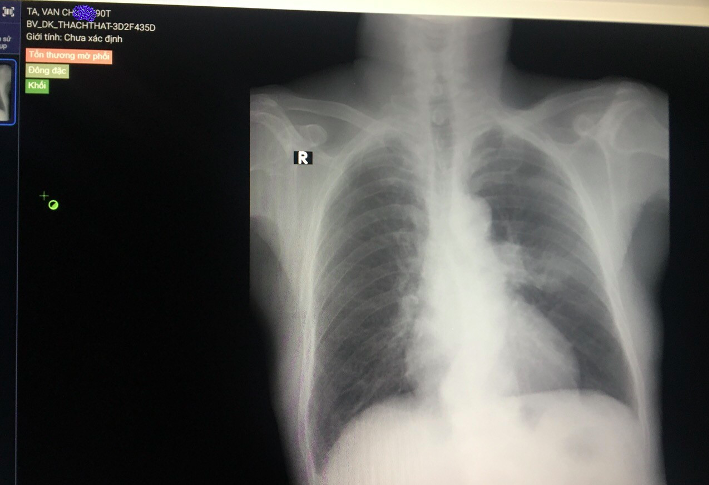

Tại đây, bác sĩ chỉ định cho ông chụp X-quang ngực thẳng. Phần mềm chẩn đoán hình ảnh có tích hợp AI (trí tuệ nhân tạo) nhanh chóng rà soát, đưa ra nhận định người đàn ông này bị tổn thương mờ phổi, đông đặc dạng khối.

Trên cơ sở cảnh báo của phần mềm, bác sĩ một lần nữa kiểm tra lại và gửi đi làm thêm các thăm dò khác. Bệnh nhân được chẩn đoán bị ung thư phổi.